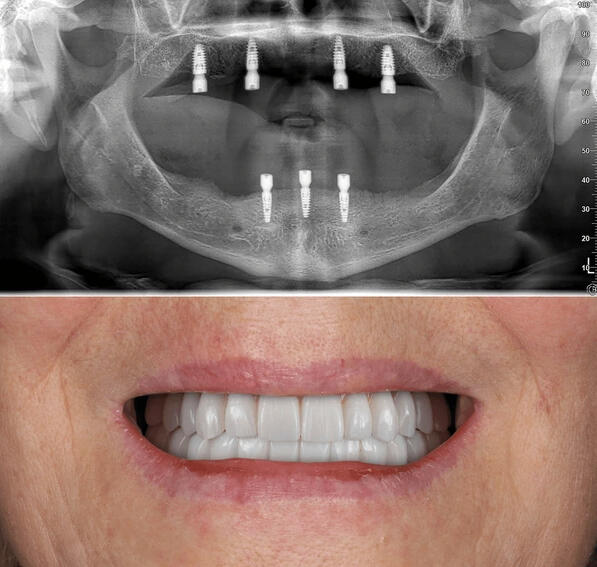

Unveiling Stunning Smile Transformations with Dental Implants